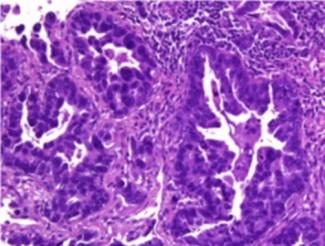

Microfotografía de tumor de origen desconocido identificado como cáncer de pulmón usando el test EPICUP®. (Foto: IDIBELL)

El cáncer de origen desconocido representa el 10% de los tumores humanos en los que se detecta la metástasis, pero no es posible localizar el tumor primario a pesar de realizarse distintas pruebas exploratorias. Como se desconoce de qué tipo de tumor se trata, la supervivencia de estos pacientes es muy corta.